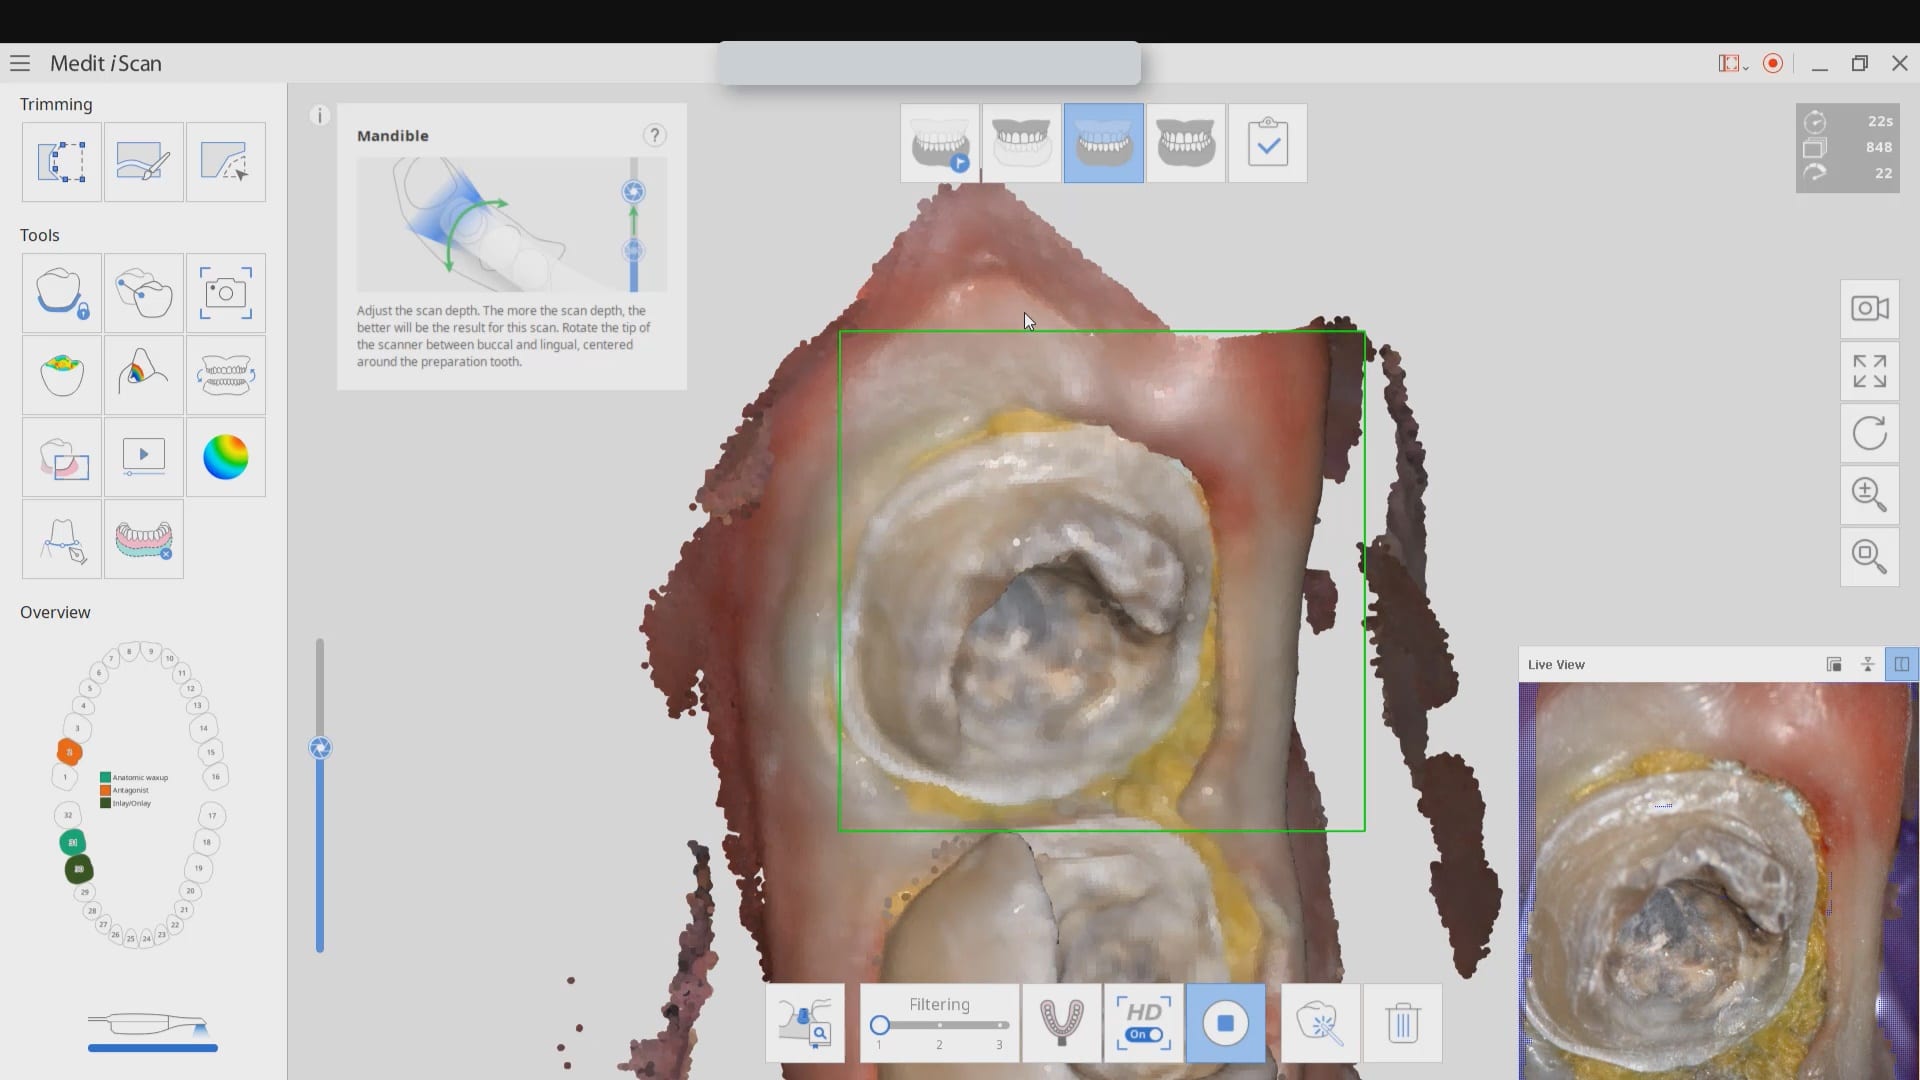

Exposing and Correcting the Distal Margin Scan

In this video we demonstrate some of the most common problems associated with second molar impressions. Usually the distal margins can be blurred by the presence of hemorrhaging or soft tissue. In this particular case, we use the tip of the camera to displace the tissue and digitall correct an area for better accuracy. The isolite systemisolite systemisolite system does a great job controlling the tongue and the lips and with proper retraction you can image a quadrant in very little time